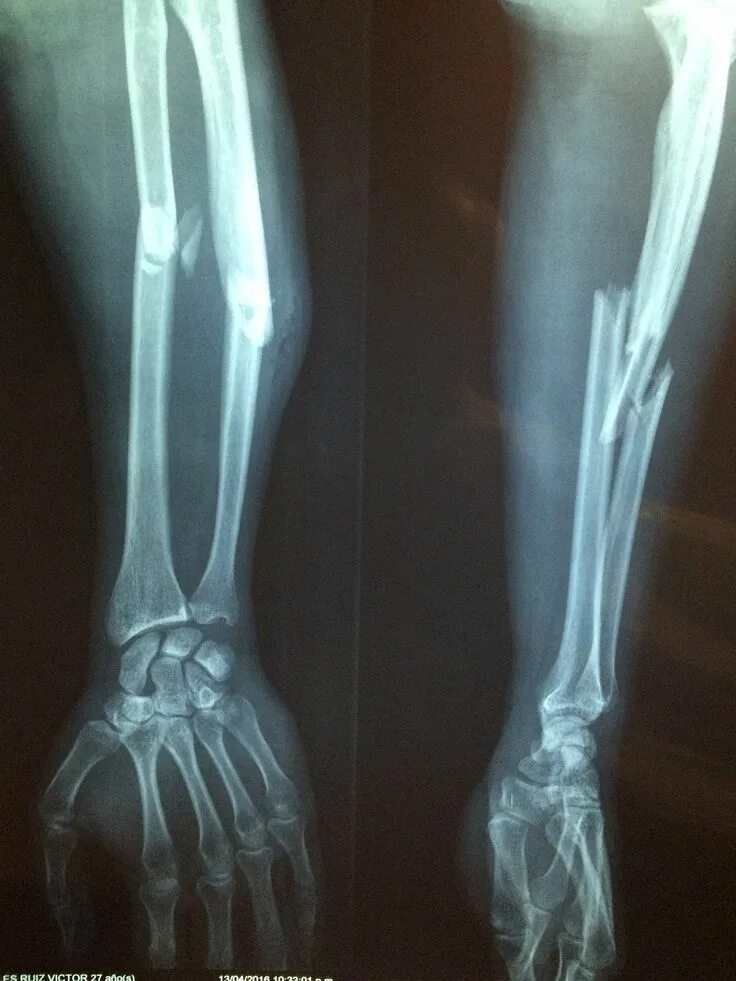

A fracture is a broken bone